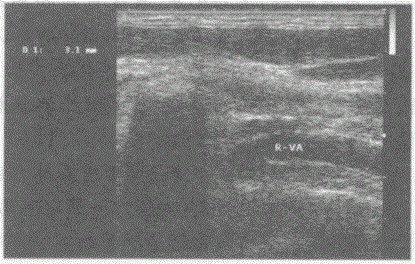

请指出下图所显示的是右椎动脉哪一段:见下图及彩图。{图1}A.右椎动脉颅内段B.右椎动脉椎间段C.右椎动脉入椎前段D.右椎动脉基底段

选项 A.右椎动脉颅内段 B.右椎动脉椎间段 C.右椎动脉入椎前段 D.右椎动脉基底段

答案 C